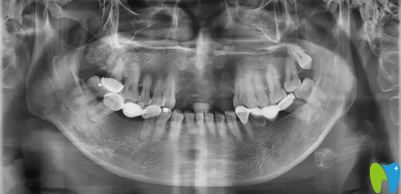

從全景和CBCT片顯示,路女士前牙區(qū)牙槽骨較薄,種植體難以“立足”,而且前牙承擔(dān)面部美觀功能,對后期的修復(fù)體要求比較高。綜合考慮后,孔主任為她制定了“以三抵五”的個(gè)性化種牙方案:在前牙缺失區(qū)域種植3顆骨結(jié)合性、身材小巧”的瑞士百丹特種植體,再利用植體做支點(diǎn),安上5顆全瓷橋修復(fù)體。路女士對孔醫(yī)生為自己制定的修復(fù)方案相當(dāng)滿意。很快,孔醫(yī)生就為她種下了3顆植體。